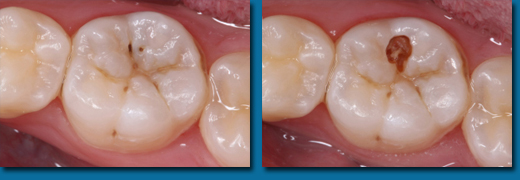

子供の出てきたばかりの歯は溝が深く虫歯になりやすい状態にあります。深い溝に接着力のある樹脂を流し込んで虫歯にならないようにすることをシーラントといいます。溝の深さには個人差がありますがリスクの高い歯には積極的にシーラントを行います。